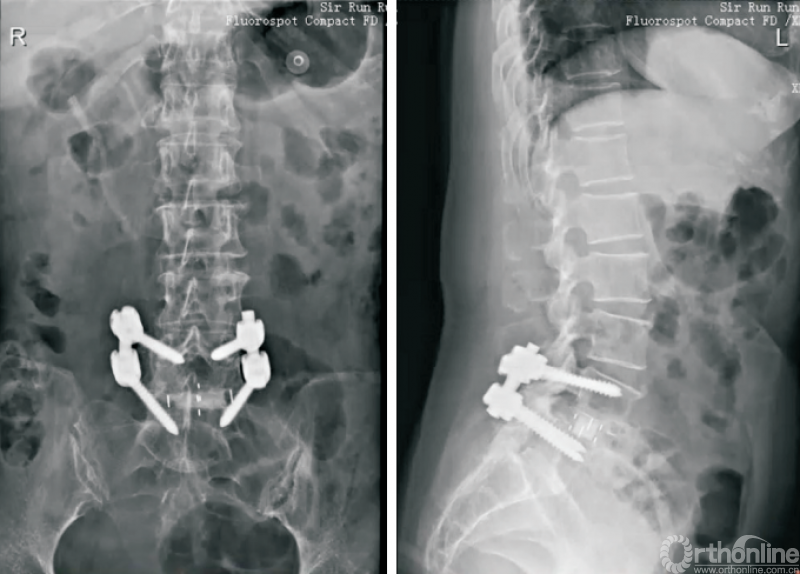

OLIF联合后路固定(图1)是治疗脊柱滑脱等失稳性疾病的经典方式[5-9],在有效减压、恢复脊柱稳定性的同时,可以避免后方肌肉、韧带等结构的损伤。相关的研究对比OLIF以及经椎间孔入路腰椎椎间融合术(transforaminal lumbar interbody fusion,TLIF)手术治疗退行性腰椎滑脱,结果表明,两者在改善术后疼痛等方面没有明显差异,且具有住院时间短、出血量少、术后腰痛较轻等特点[10-12]。

图1 经典的OLIF

CHUNG等[13]的研究表明,相较于前入路腰椎椎间融合术(anterior lumbar interbody fusion,ALIF)手术,OLIF在恢复椎间隙高度及节段前凸方面更加具有优势;葛腾辉等[14]研究证实,OLIF联合后路固定治疗退行性腰椎滑脱能进一步减少腰椎退行性滑脱患者的滑移率,并增加手术节段前凸角度。

俞仲翔等[6]研究证实,对于邻椎病的治疗,OLIF可以取得与后路腰椎椎间融合术(posterior lumbar interbody fusion,PLIF)等经典手术方式同样的效果,且能够缩短手术时间,减少并发症的发生。王志强等[15]研究证实,OLIF联合单侧或双侧的椎弓根螺钉固定均可有效治疗腰椎退行性疾病。CHO等[16]研究表明,对于存在矢状位失衡的退行性脊柱侧弯患者,OLIF联合后路螺钉治疗比传统的PLIF更加有效。因此,经典的OLIF技术可以应用于脊柱侧弯、脊柱滑脱、腰椎椎管狭窄等众多腰椎退行性疾病的诊疗。